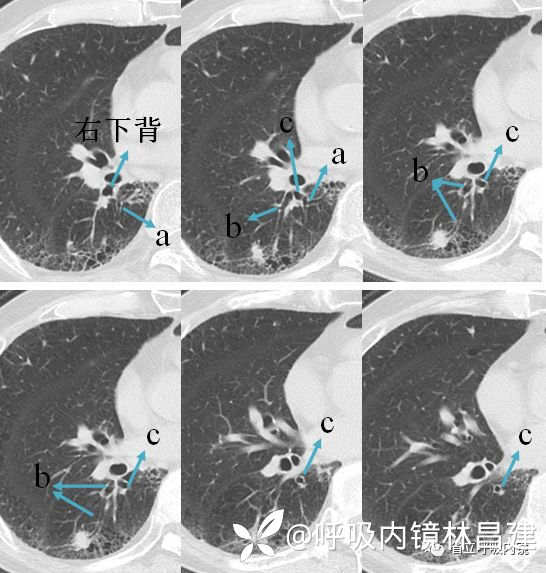

看右下叶背段支气管树可知,a、c亚段均靠近脊柱及纵隔,不同的是一个是向上走形,一个是向下走形,b亚段是远离脊柱及纵隔的向外侧发散,因此它又叫外侧支。命名顺序按照逆时针方向。

CT从上而下,依次出现a、b、c亚段。由于a亚段支气管走形是垂直于水平面的,因此CT上你可以看到一个小圆环结构,b亚段是平行于水平面的,因此CT上是呈现柱状双轨征,c亚段大多斜行于水平面,因此CT上可能呈现类似于环形跑道结构(只是打个比喻,每个人的支气管树结构变化很大,不一定都是规规整整的,有点扭曲,有个分支都是很常见的,但是先把标准的学会,再学异常的,你就能游刃有余了)。

只看这一张你是很难定位的,你需要前前后后,不断翻看,才能进行三维重建。CT从上而下,依次出现a、b、c亚段。由于a亚段支气管走形是垂直于水平面的,因此CT上你可以看到一个小圆环结构,b亚段是平行于水平面的,因此CT上是呈现柱状双轨征,c亚段大多斜行于水平面,因此CT上可能呈现类似于环形跑道结构(只是打个比喻,每个人的支气管树结构变化很大,不一定都是规规整整的,有点扭曲,有个分支都是很常见的,但是先把标准的学会,再学异常的,你就能游刃有余了)。